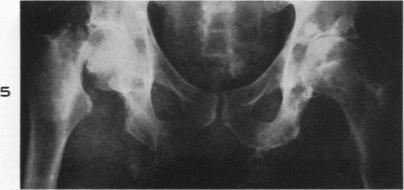

Pathologic changes in gout; survey of eleven necropsied cases.

Am J Pathol. 1956 Sep-Oct;32(5):871-95.